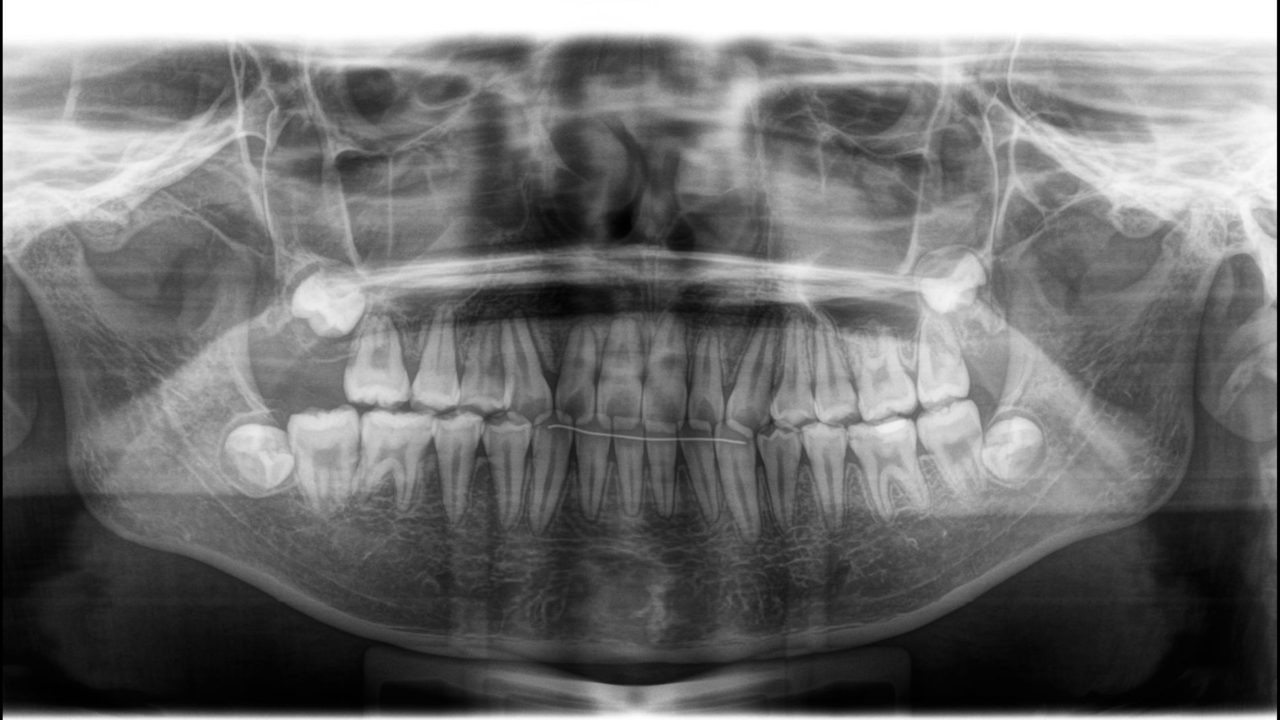

初診レントゲン

| 備考 | 右上第1大臼歯の自発痛で来院されました。 マイクロスコープ下の精密根管治療を行えば、十分改善する見込みはありました。 しかし、14歳と若く、長期的な予後は不安でした。 前歯の歯列、咬合不正があったため、全顎矯正を提案しました。 全顎矯正ができれば、予後不良な右上第1大臼歯を抜歯して、親知らずを活かせます。 そうなれば、神経の死んだ歯はなくなり、歯の数も減りません。 14か月で矯正治療が終了したため、まだ親知らずは萌出していませんが、レントゲン的にはいい位置に来そうです。 注意深いメインテナンスを行っています。 |